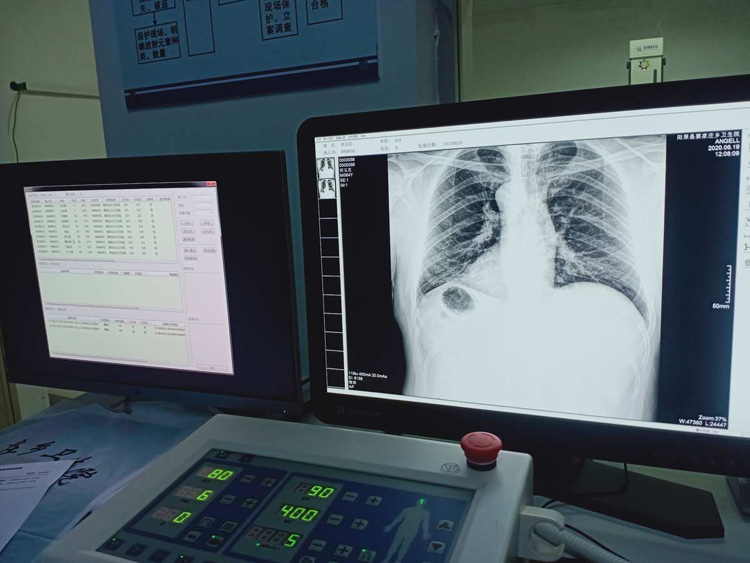

平床DR的平板探測器可以拍攝到高清的數字圖像??梢詸z查身體的某個部位。頭部、胸部、腹部、上肢、下肢、正位、側位、都可以正常的拍攝。很小的劑量就可以采集到高清的檢查圖像。平板的穩定性也非常的強。DR的平板探測器跟圖像結合。噪音低、圖像的畫質呈現豐富。圖像的信息量會跟多提供給醫生參考。幫助醫生提高診斷的準確性。Digital Radiography就是數字化拍攝。平板探測器特性會對拍攝片的圖片質量有關系。

平床DR的數字影像高分辨率,動態范圍比較大,密度密度分辨率高可以看到更多細節。拍攝的速度快偽影小。比X光的的靈敏度高很多。輻射小的能量就可以拍到清晰的圖像。輻射量少30%以上。特別是對骨頭軟組織的效果更優。對結節的有沒病變的檢測查出率更高。